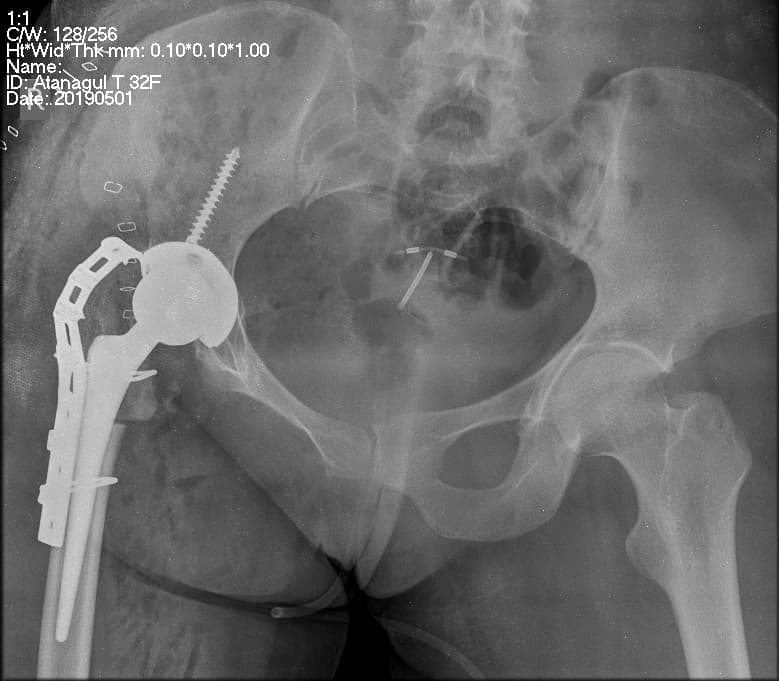

Түнхний үе солих мэс засал гэж юу вэ image3

Мэс заслын өмнөх болон дараах рентген зураг